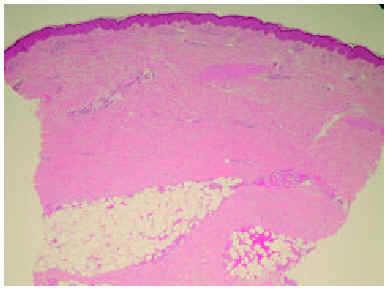

Una biopsia cutánea de la pierna mostró cambios compatibles con una esclerodermia (figs. 2 y 3). Destacaba una dermis engrosada formada por haces de colágeno engrosados y ausencia de anejos cutáneos, así como un engrosamiento y fibrosis de los septos interlobulillares del tejido celular subcutáneo.

Fig. 2.--Dermis engrosada compuesta por haces de colágeno esclerótico y atrofia de los anejos. (Hematoxilina-eosina, x10.)